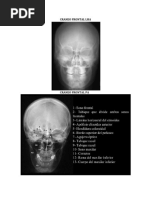

CRANEO AP

Estructuras mostradas: Simetra entre el borde lateral del crneo y las orbitas, bordes del peasco simtricos, peascos ocupando las orbitas, hueso frontal sin excesiva densidad en los bordes. Totalidad del vrtice craneal

CRITERIOS DE EVALUACIN Estructuras mostradas: Crneo sin rotaciones ni inclinaciones, mitades craneales superpuestas, ausencia de rotacin de la silla turca, ausencia de superposicin de la columna vertebral sobre mandbula.